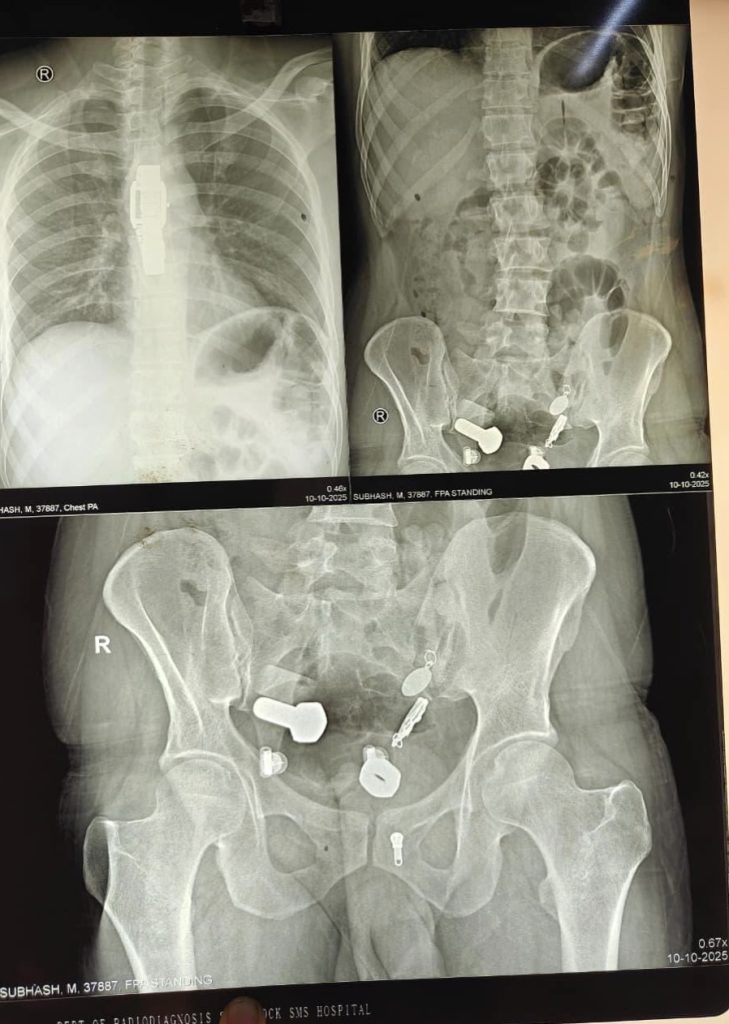

When doctors performed X-ray scans, they were stunned to find a wristwatch lodged in his oesophagus, along with iron fragments, nuts, and bolts trapped in his large intestine.

Initially, medical staff attempted to remove the objects through an endoscopy, but the procedure failed due to the number and size of the items. Surgeons were later forced to perform a three-hour operation to remove everything from his digestive system.

The bizarre operation took place on October 9th at Sawai Mansingh Hospital in Jaipur, where the patient had been admitted after his condition worsened.